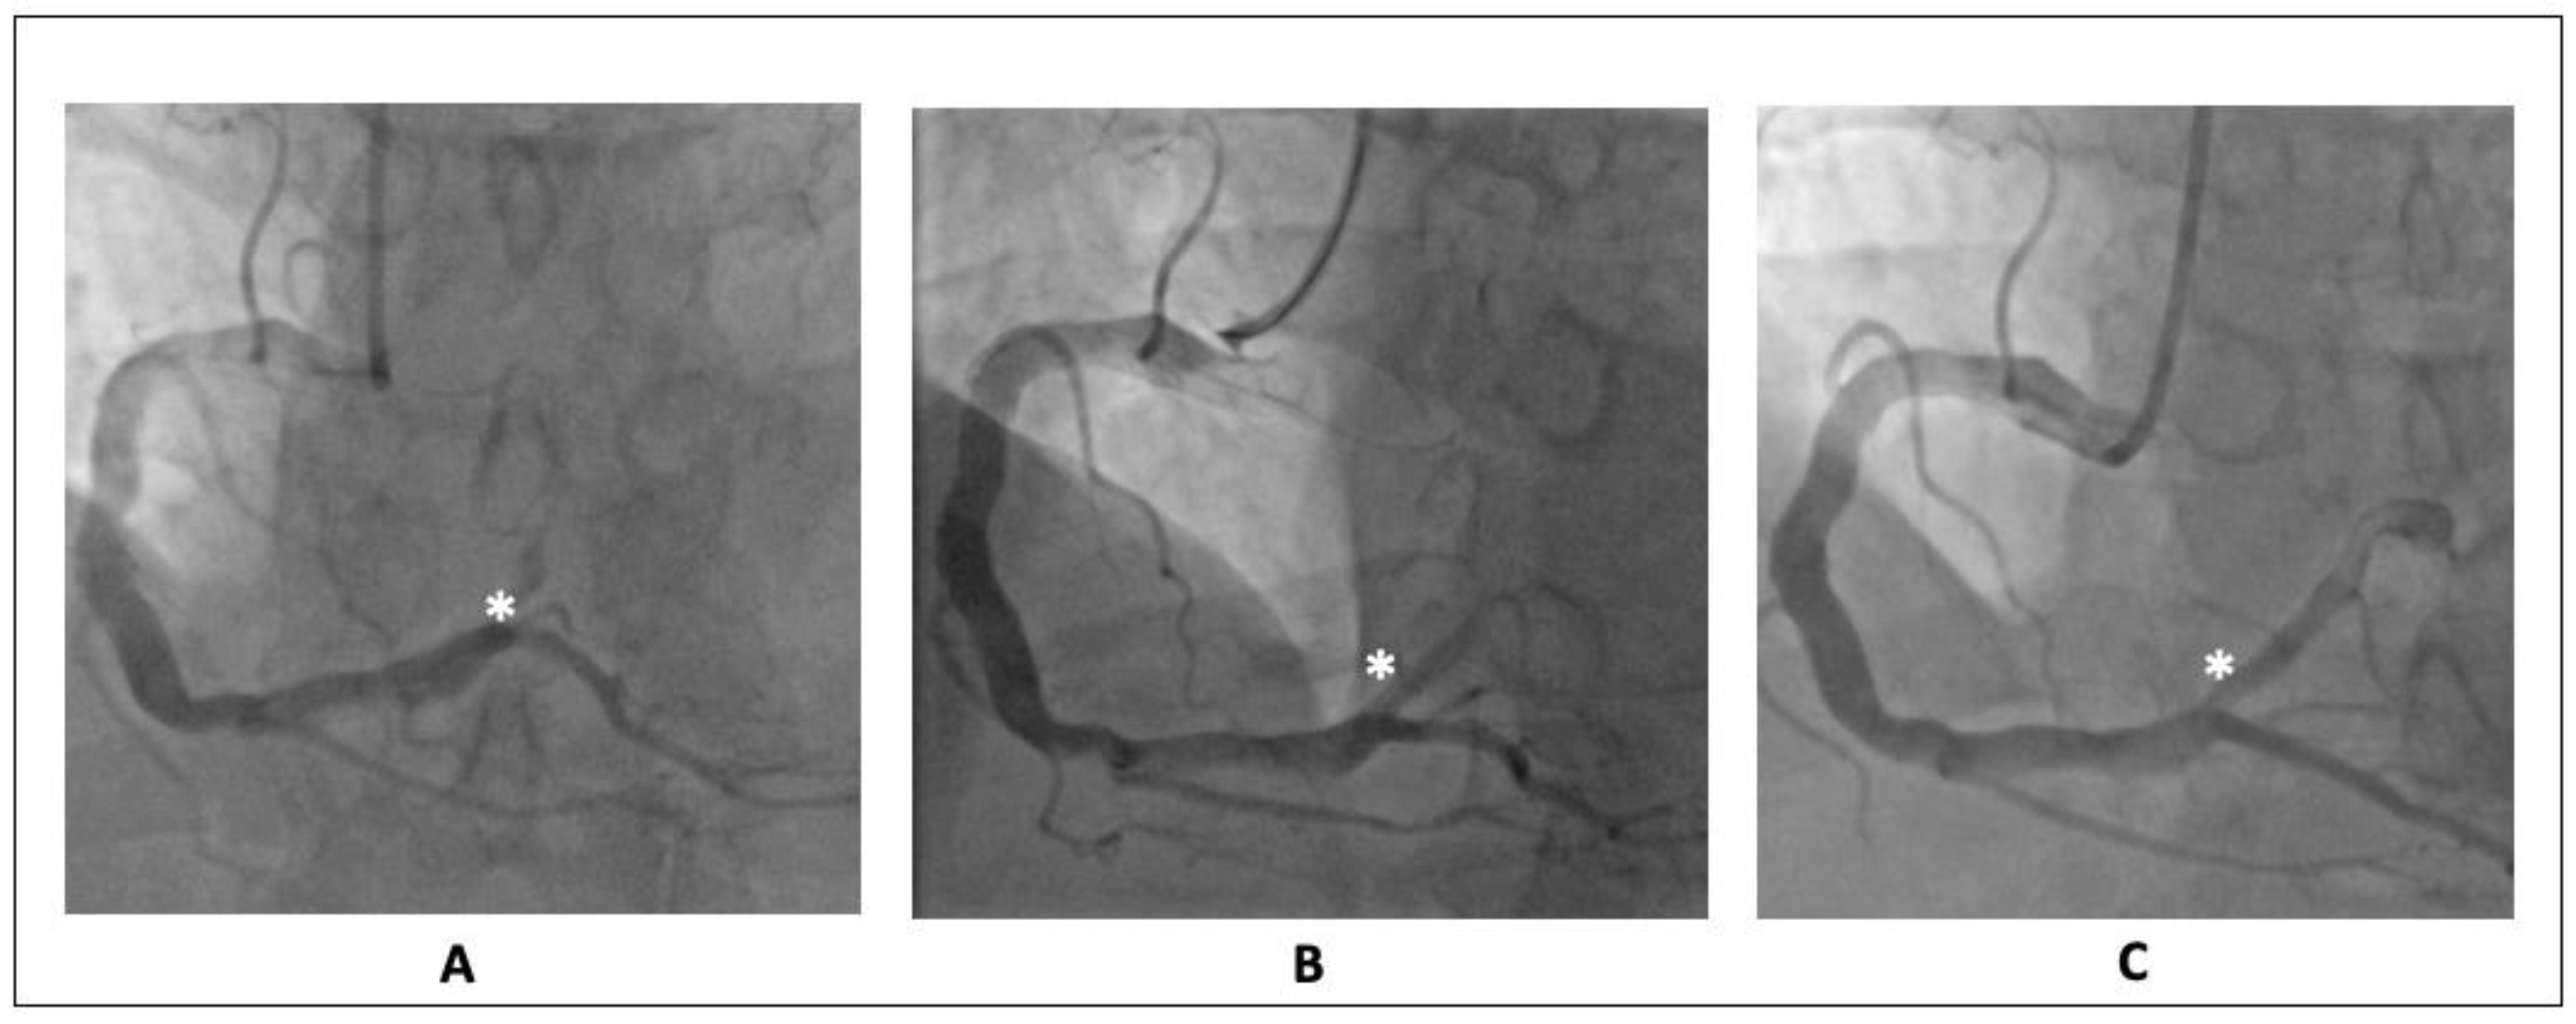

7. Case 2